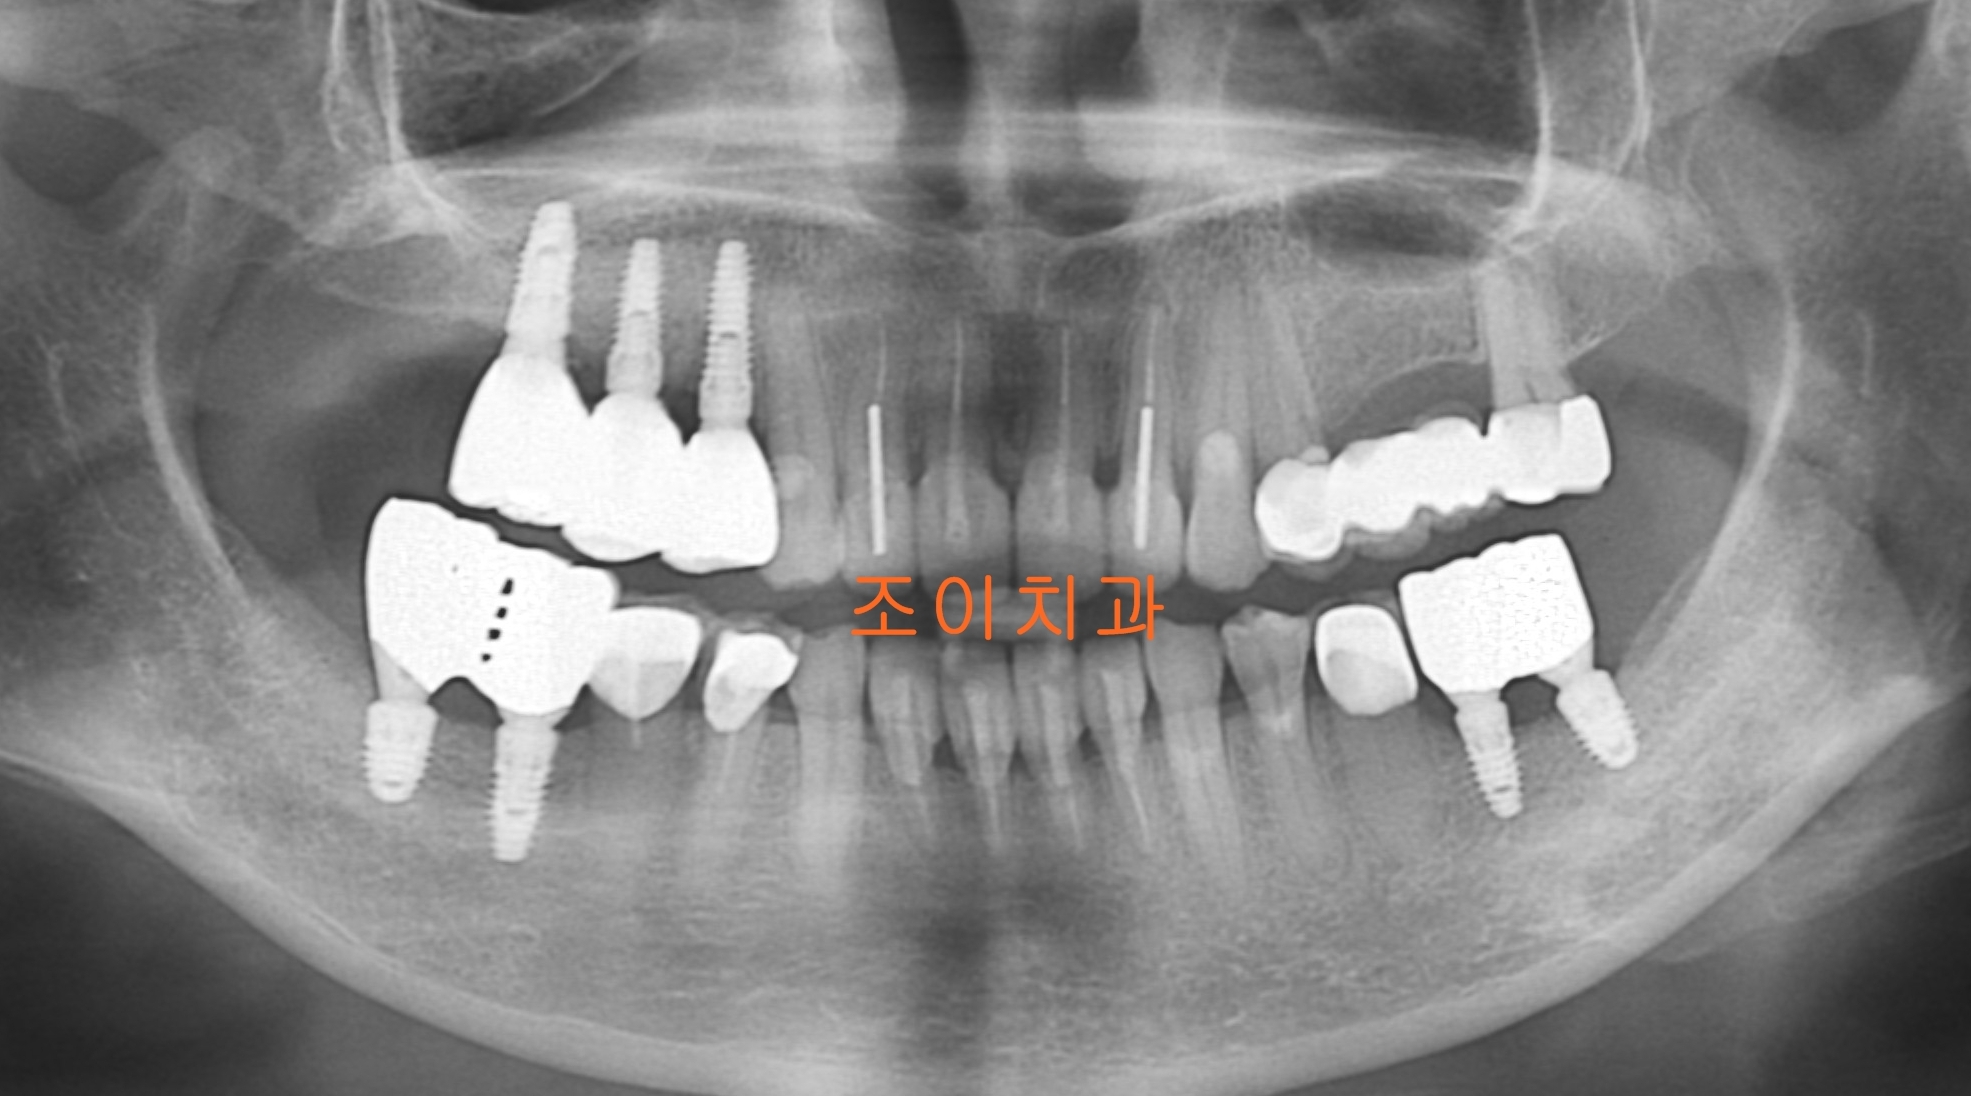

[임플란트] 제목 : 앞니 보철 및 임플란트

임플란트 상하